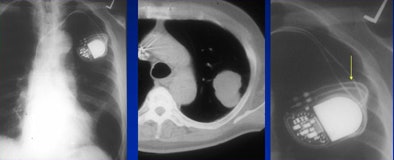

|  |

| False-positive: Hypertrophic costochondral junction misread as a lung mass. |